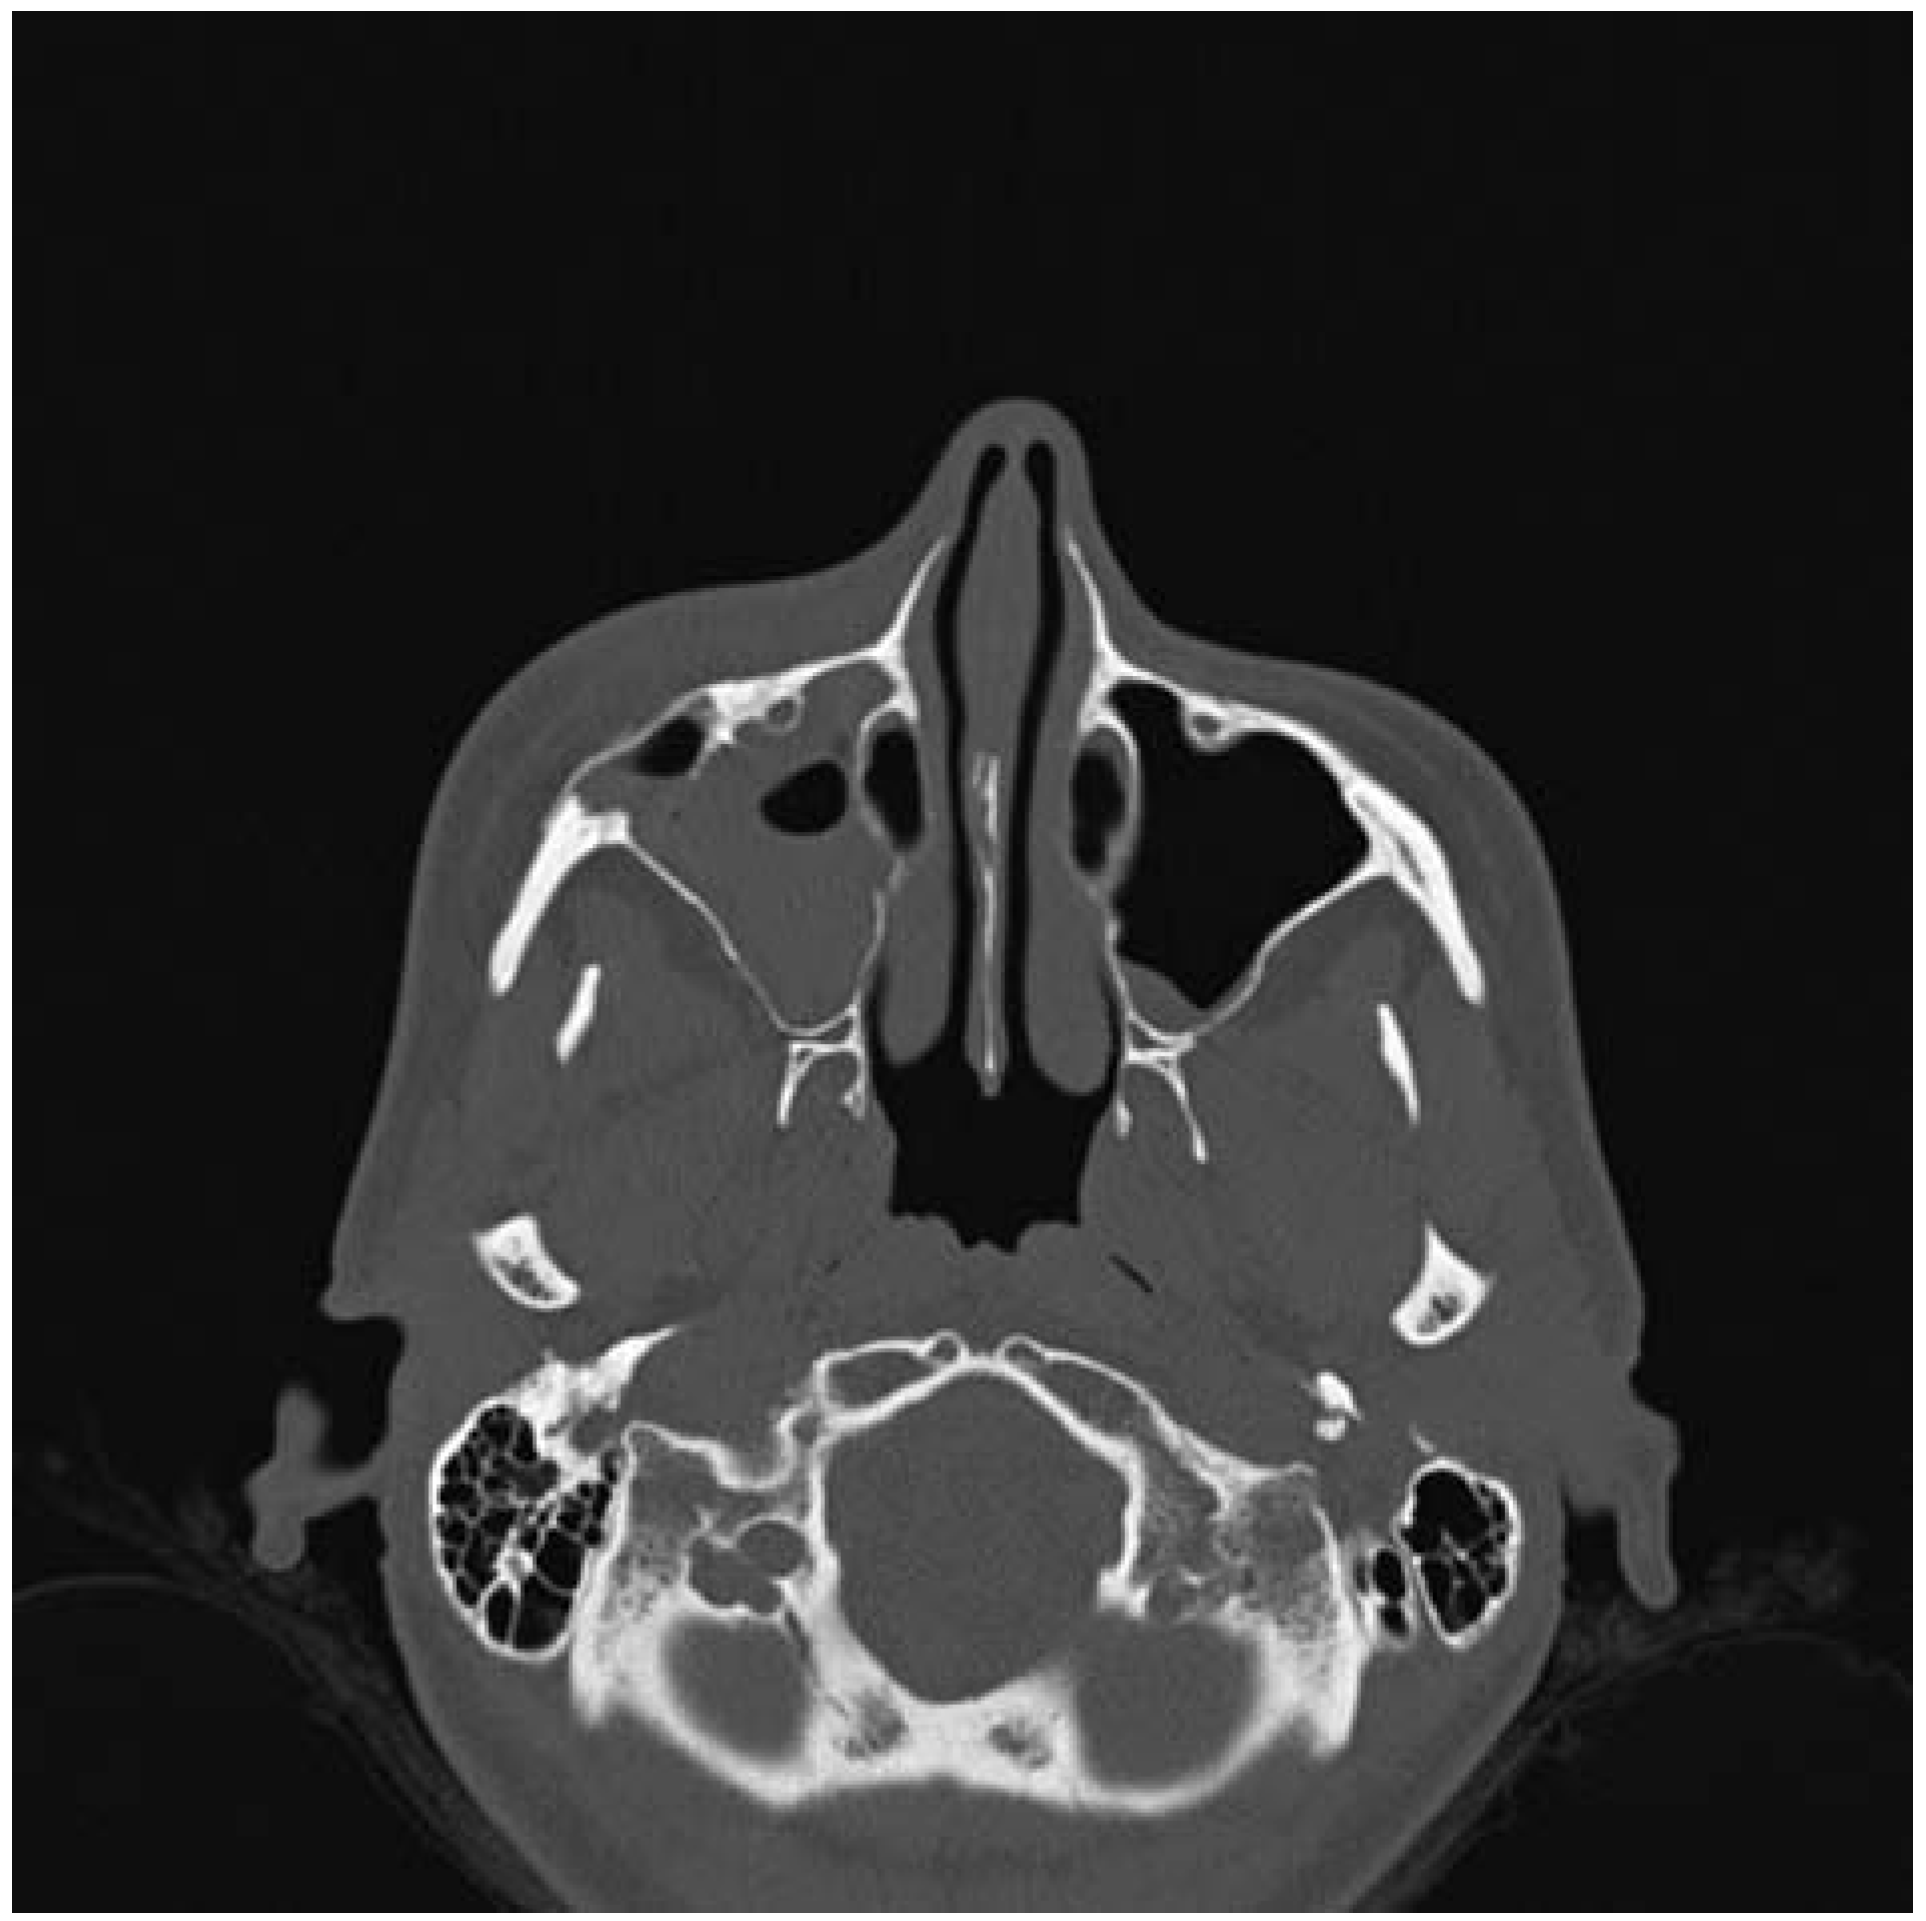

:Case Presentation

- Moore, S.L.; Chun, J.K.; Mitre, S.A.; Som, P.M. Intraosseous hemangioma of the zygoma: CT and MR findings. AJNR Am J Neuroradiol 2001, 22, 1383–1385. [Google Scholar] [PubMed]

- Razek, A.A. Imaging appearance of bone tumors of the maxillofacial region. World J Radiol 2011, 3, 125–134. [Google Scholar] [PubMed]